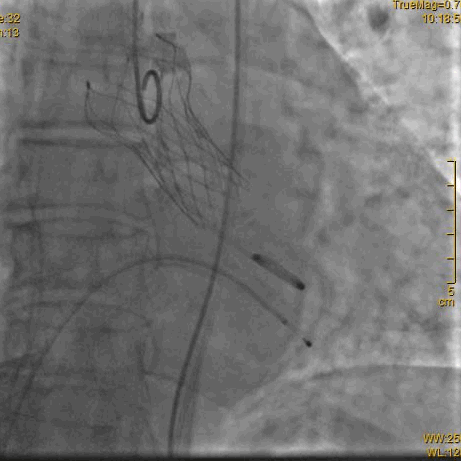

主动脉根部造影,冠脉开口保护

释放到1/3处造影

释放到回收极限造影

瓣膜完全释放后造影,形态良好,无瓣周漏